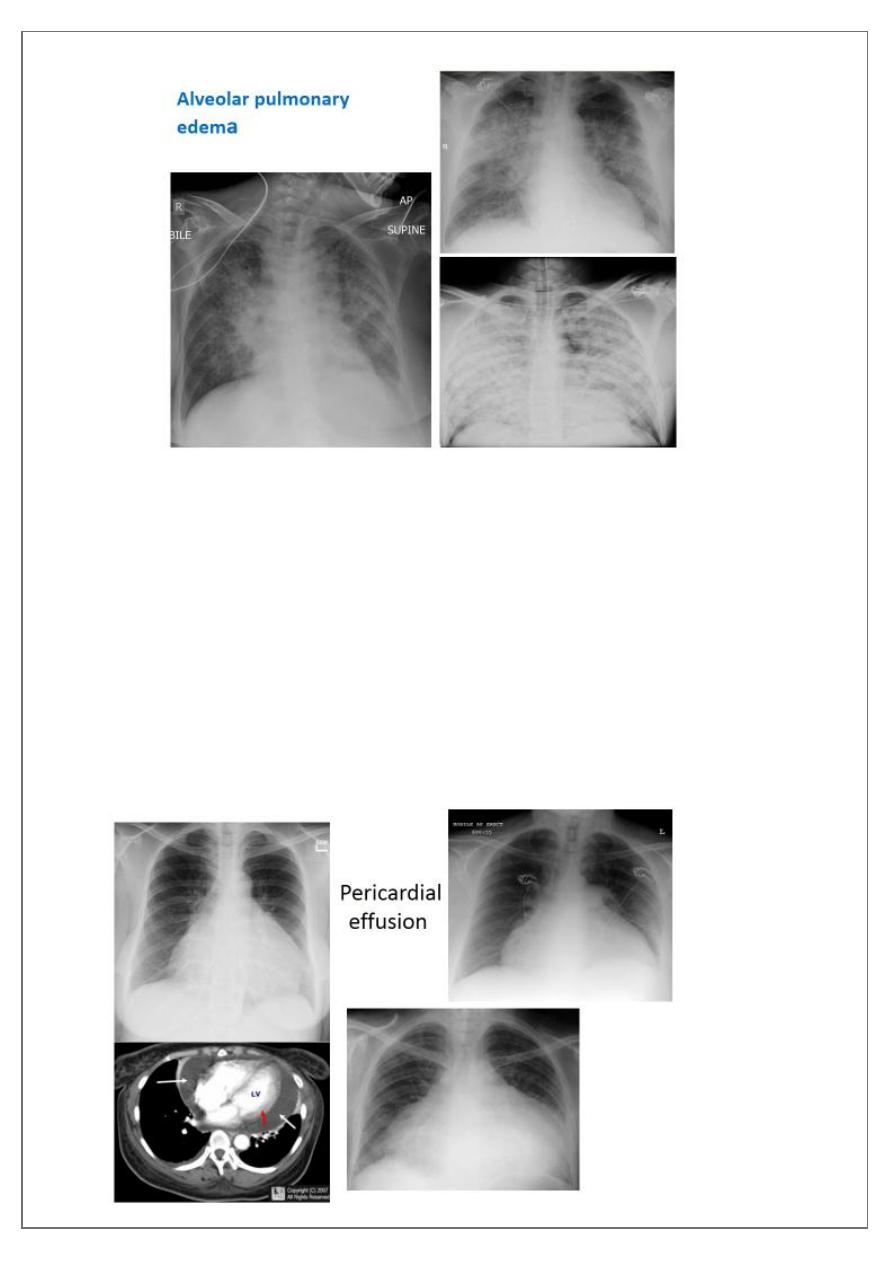

Pulmonary edema

is a broad descriptive term and is usually defined as an abnormal

accumulation of fluid in the extra-vascular compartments of the lung .

radiograph include if pressure > 25 mmHg the findings of :

2. bat wing pulmonary opacities

Pericardial effusions

occur when fluid collects in the pericardial space (a normal

pericardial sac contains approximately 30-50 mL of fluid).

Radiographic features

Plain radiograph

a very small pericardial effusion can be occult on plain film there can be globular

enlargement of the cardiac shadow giving

shape heart or pumpkin shape heart